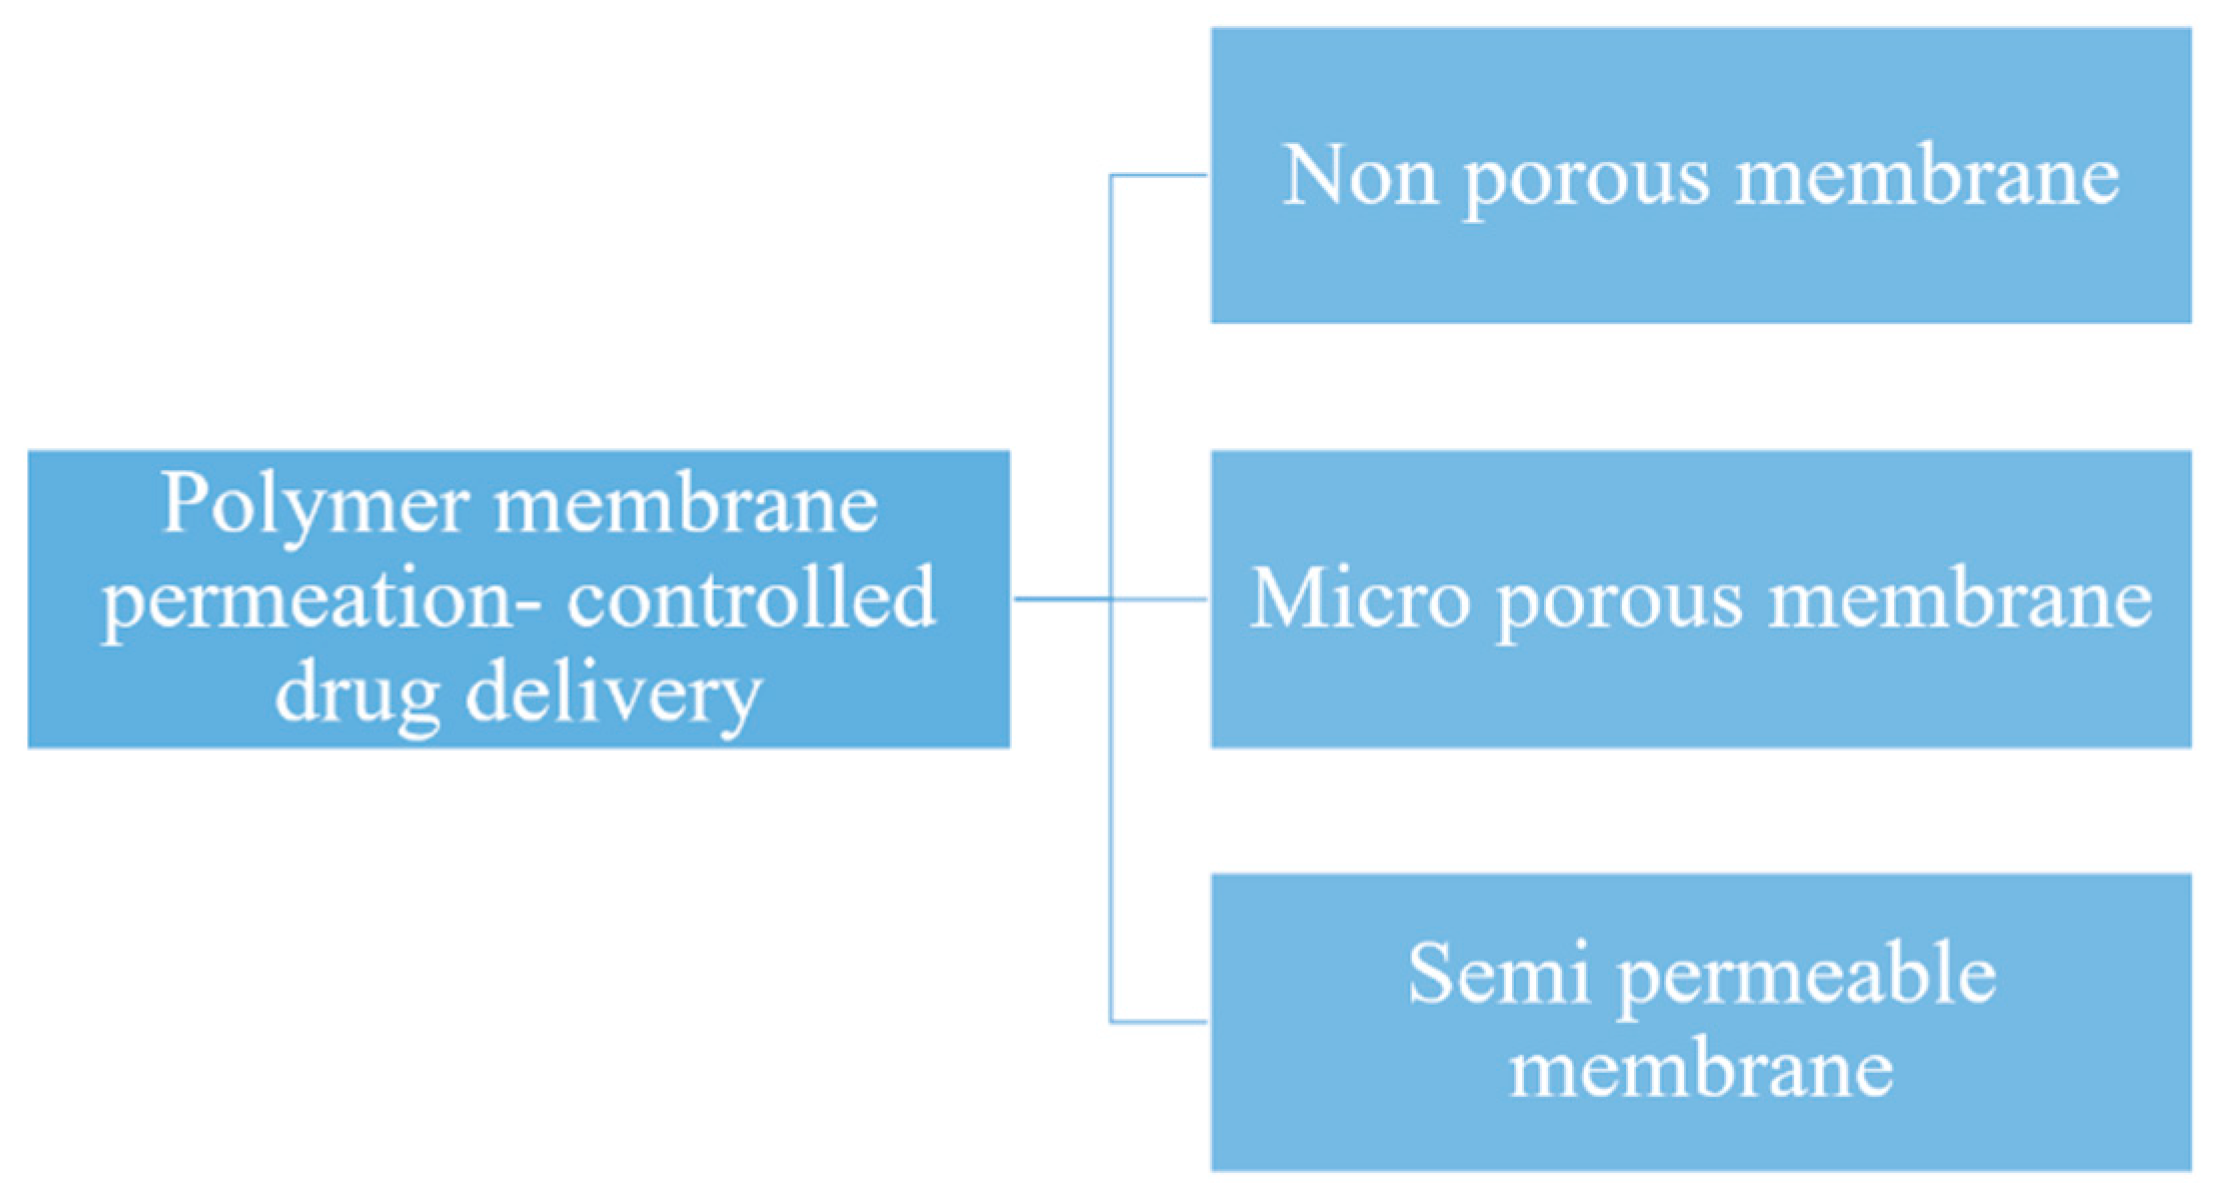

5.1. Membrane Classifications

5.2. Drug Delivery by Membranes

5.2.1. Polymeric Membranes